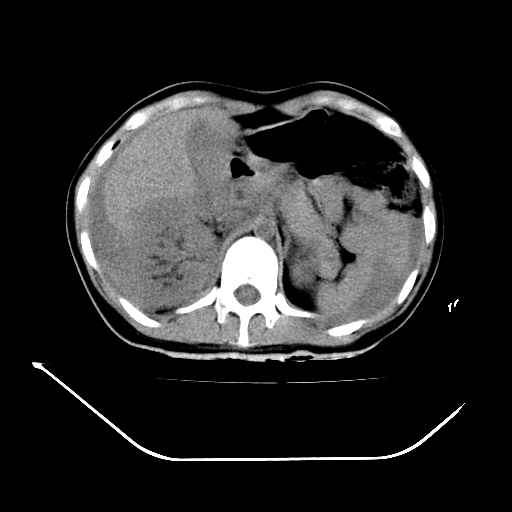

以下是引用liuyue在2008-7-19 13:02:00的发言:[br]1.肝右叶后下段及右肾挫裂伤伴腹腔积血。[br]2.右侧多发性肋骨骨折、横突骨折、右髂骨骨折伴周围软组织挫伤。[br]3.右侧腰大肌肿胀,并可见低密度影,如为气体,则肠道挫裂伤待除外。

以下是引用zhengfaming在2008-7-19 14:42:00的发言:[br]1.肝右叶后下段及右肾挫裂伤伴腹腔积血。脾脏挫裂伤待排[br]2.右侧多发性肋骨骨折、横突骨折、右髂骨骨折伴周围软组织挫伤。[br]3.右侧腰大肌肿胀,并可见低密度影,如为气体,则肠道挫裂伤待除外

以下是引用道哥在2008-7-19 16:52:00的发言:[br]肝右叶后下段及右肾挫裂伤、脾破裂伴腹腔积血。[br]2.双侧多发性肋骨骨折、横突骨折、右髂骨骨折伴周围软组织挫伤。[br]3.右侧腰大肌肿胀,并可见低密度影,如为气体,则肠道挫裂伤待除外。